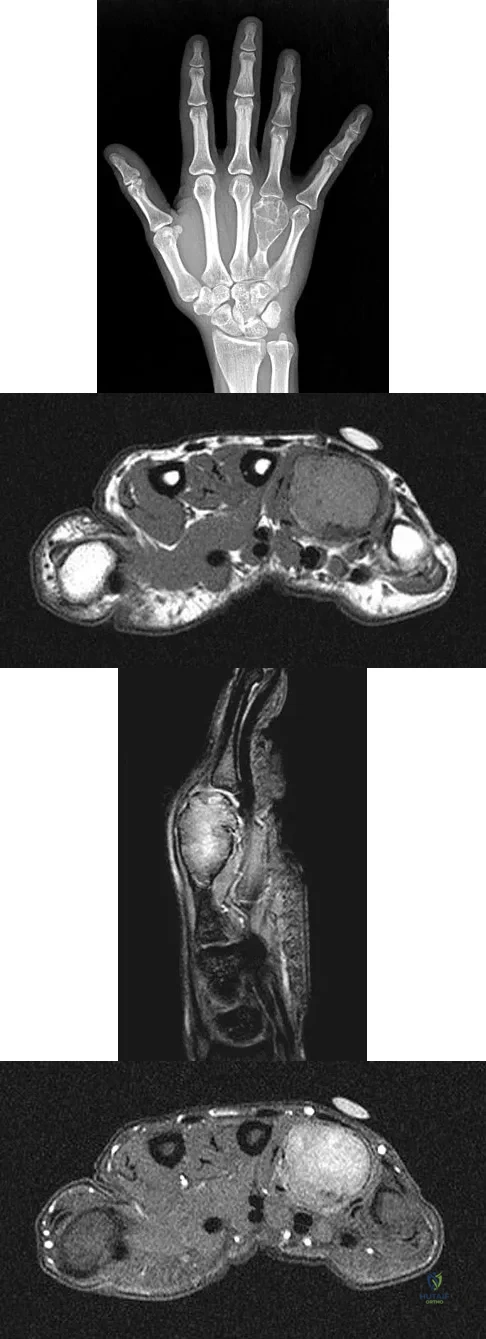

A 26-year-old man has had hand pain and progressive swelling in the knuckle for the past several months. He denies any trauma to the hand. The ring finger metacarpophalangeal joint is tender, and there is loss of motion in the digit. Figure 32a shows the radiograph and Figures 32b through 32d show the T1-weighted, T2-weighted, and gadolinium MRI scans, respectively. What is the most likely diagnosis?

A 17-year-old boy has had a mass in his right thigh for the past 6 months. He denies any history of trauma. Examination reveals that the mass is painless and firm. A radiograph and axial MRI scan are shown in Figures 49a and 49b. What is the most likely diagnosis?